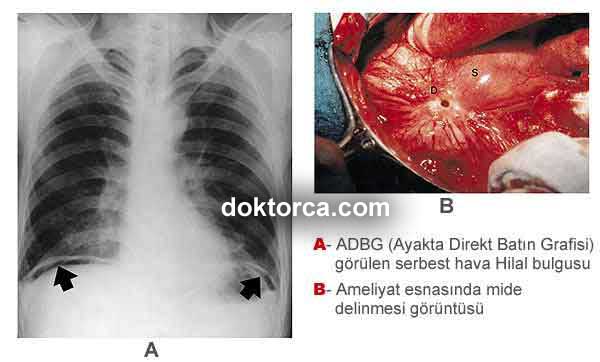

Diyafragm altında görülen serbest hava (subdiyafragmatik ters hilal bulgusu) PA Akciğer Grafisinde daha net bir şekilde görülür.